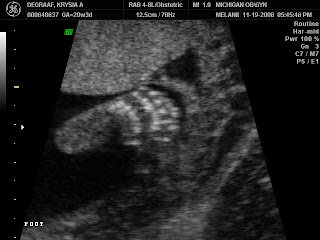

IT'S A GIRL!!!

So here's the money shot (I hope this is that last anyone ever sees of this!). As soon as Melanie (the ultrasound tech) put her little wand on my belly looking for it, I knew. I said, "Is that what I think it is?" She asked what I thought it was. Well, I've been around enough preggers to know that 3 white lines indicates a girl. And I was right! Here's the proof that I'm having a girl!